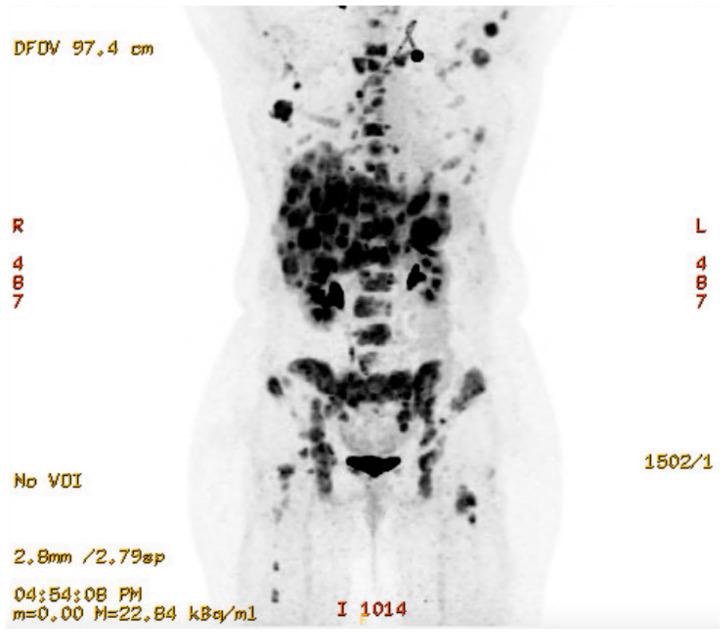

Ectopic adrenocorticotropic hormone syndrome (EAS) occurs when a tumor develops neuroendocrine differentiation with the secretion of ACTH resulting in hypercortisolism and possibly Cushing's syndrome (CS). Only 5-10% of CS cases are attributed to EAS; of these, breast tumors comprise less than 1%. Two known variants of breast neuroendocrine tumors include neuroendocrine-differentiated carcinoma and ductal carcinoma with neuroendocrine features. Currently, guidelines for treatment are limited and EAS is associated with significant morbidity and mortality. A 39-year-old female presented with a rapidly enlarging breast mass. Biopsy demonstrated invasive poorly differentiated breast carcinoma with high-grade neuroendocrine features and necrosis. Staging at diagnosis confirmed metastatic disease of the liver and bone. First-line chemotherapy (Cisplatin/Etoposide/Durvalumab) was initiated with evidence of disease progression after four cycles. Given a poor response to therapy, a simple mastectomy was performed for local control and complete pathologic analysis, demonstrating high-grade neuroendocrine carcinoma with large-cell features. Second-line therapy (Adriamycin/Cyclophosphamide) was initiated for three cycles after which the patient required admission for severe and refractory hypokalemia. Workup confirmed elevated ACTH consistent with paraneoplastic EAS and further evidence of disease progression. Third-line therapy (Nab-Paclitaxel) was initiated, and genetic testing was completed, confirming the PIK3 mutation, for which access to Alpelisib therapy was requested. Given symptoms of progressive severe CS with significant liver disease limiting medical therapies, the patient underwent urgent bilateral laparoscopic adrenalectomy after which she was able to be discharged home while awaiting additional systemic therapy. EAS resulting in CS secondary to breast neuroendocrine carcinoma is a rare and challenging diagnosis. Further research is needed to inform treatment guidelines to improve outcomes. While patient survival is dependent upon the underlying disease process, laparoscopic bilateral adrenalectomy is an accepted, definitive treatment option.